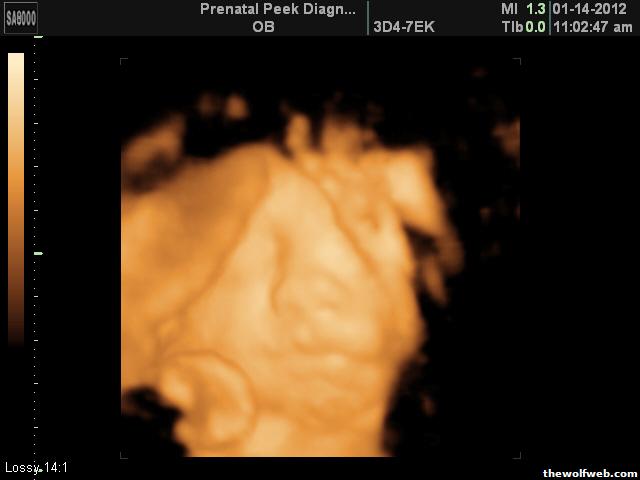

So we go Saturday to find out what the little dude looks like. I'm exited but those 4D images can be pretty creepy.

Baby Brame